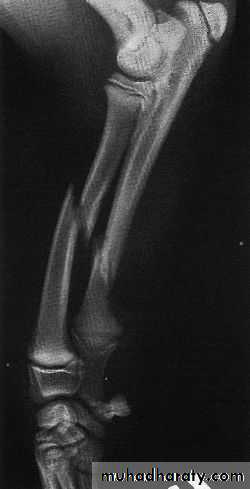

• Plain radiography : ( rule of 2 )2 Views

2 joints

2 limbs

2 occasions

2- CT scan : such as in palvic and spine fractures and in intra articular fracures